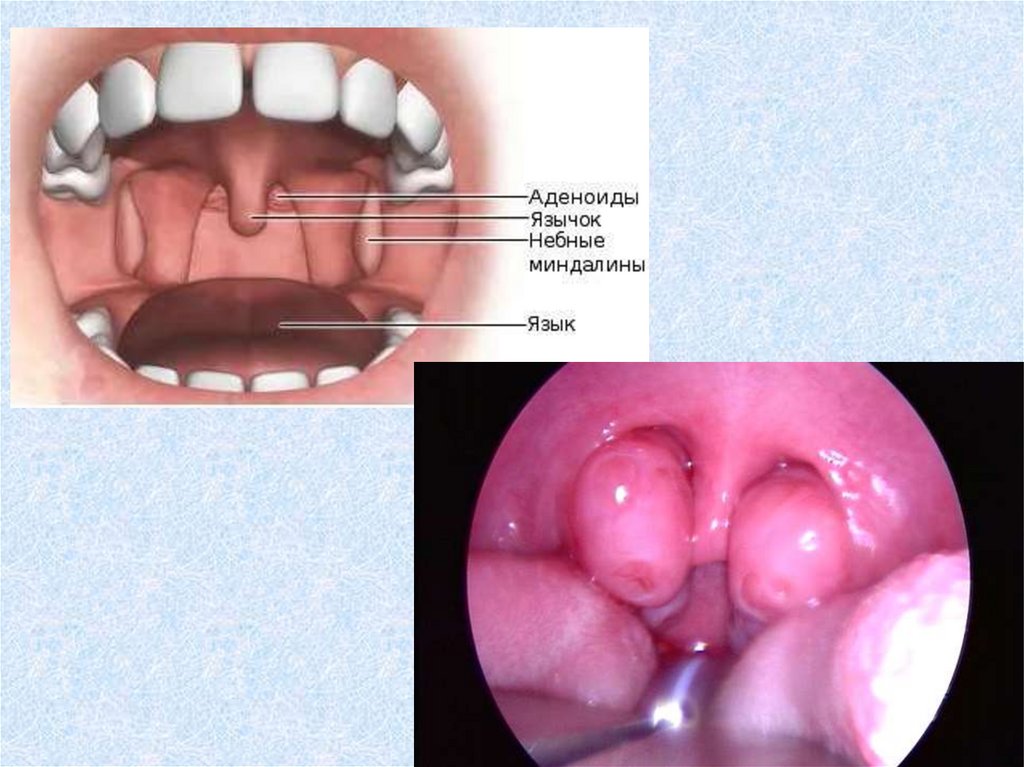

На стыке дыхательной и

пищеварительной систем для

предотвращения попадания

микробов находятся барьерыМИНДАЛИНЫ

(скопления лимфоидной ткани)

Этопериферические

органы иммунной

системы

Тонзилэктомияудаление миндалин